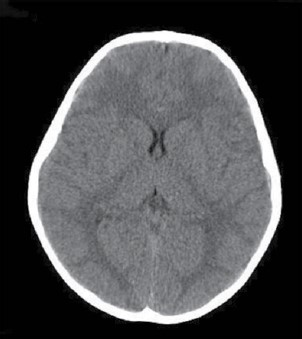

Paciente do sexo feminino com 30 anos de idade, procura serviço de neurologia com queixa de cefaleia há 6 meses, de média intensidade, holocraniana, muito frequente (diária), com piora progressiva, acompanhada de embaçamento visual e episódios de escurecimento da visão. Negou náuseas ou vômitos. Ao exame, a pacientes estava normotensa, afebril, consciente e orientada, sem sinais de localização e edema de papila bilateral na fundoscopia. Referiu 3 meses antes do início dos sintomas ter sofrido trauma crânio encefálico. Apresentou o exame de imagem a seguir. Com esses elementos, assinale a alternativa que apresenta qual seria a sua hipótese diagnóstica.